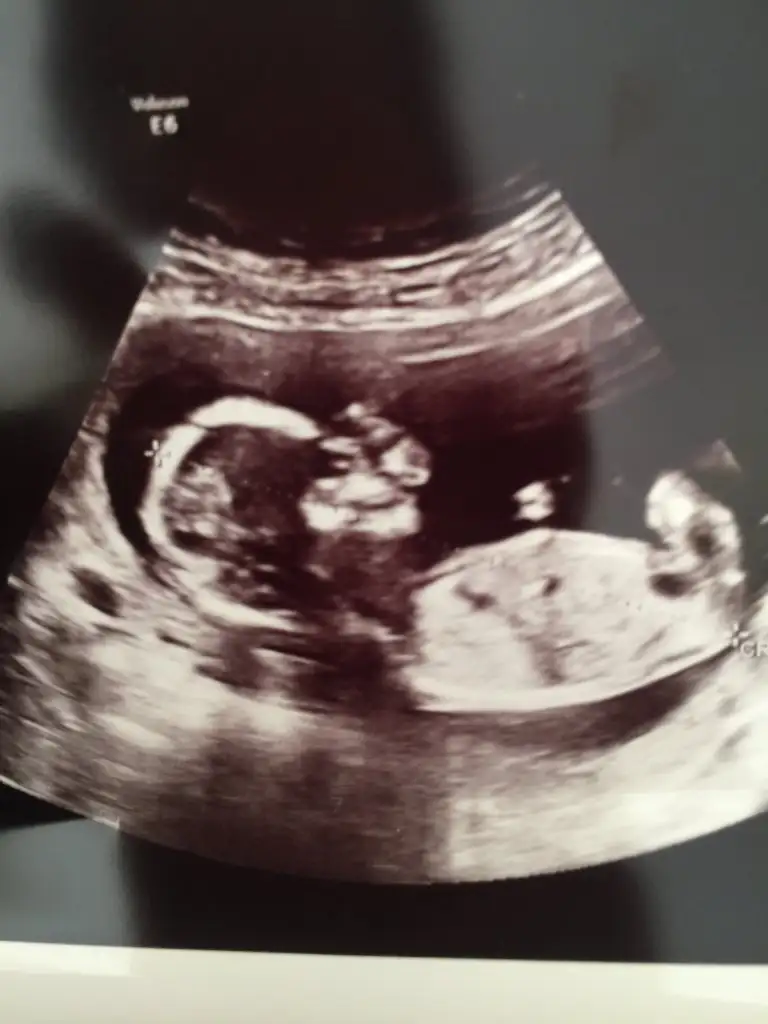

Evet erkek tahminim

Yok nuba iyi bakarsan dik ve parlak cnm Dr da erkek demisKız gibi

Kız canimBana da yorum yaparmısınız lütfen. Bugün geldim doktordan. Cinsiyeti söyledi ama kesin olarak bi ay sonra dedi

Erkek gibi ama tekrar USG istiyorumSelamIkra meyra banada yorum yapabilirmisin 11+3 teyiz Ikra meyra